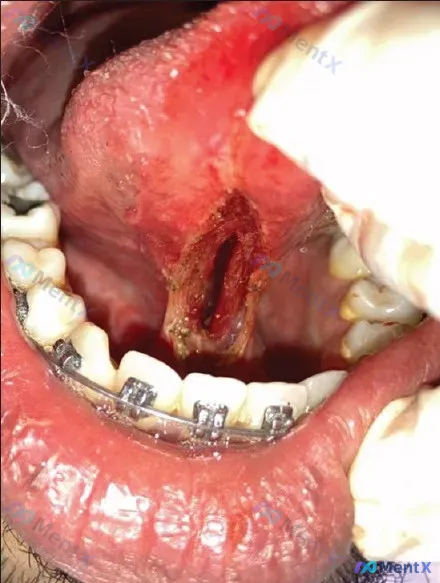

舌腹深大创面 + 颏舌肌直接暴露 + 正畸托槽:最该先处理的是什么?

- 关键影像描述:舌腹正中偏下可见长梭形开放性深创面,深凹状,无明显缝合痕迹;基底暗红,有黄白色渗出物,创缘充血水肿;最关键的一点——颏舌肌(genioglossus)可见。

- 局部背景:下前牙区佩戴有正畸托槽(牙套)。

- 其他:未见大面积坏死或明显脓性分泌物。